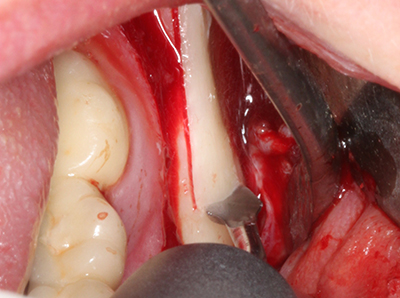

Piezo surgery has additional advantages when harvesting bone blocks. In addition to the high precision with osteotomy described above, the use of the thin saw tips specifically minimizes loss of material. Greater loss of material during harvesting can be expected with the thicker instrument tips, particularly when using Lindemann drills (Lakshmiganthan, Gokulanathan et al. 2012). The basal separation, which is necessary particularly for retromolar block transplants, is simplified by specially designed rectangular saws, with the result that piezo surgery is viewed as a precise, simple and safe procedure for harvesting retromolar bone blocks (Happe 2007) (Fig. 1-12).